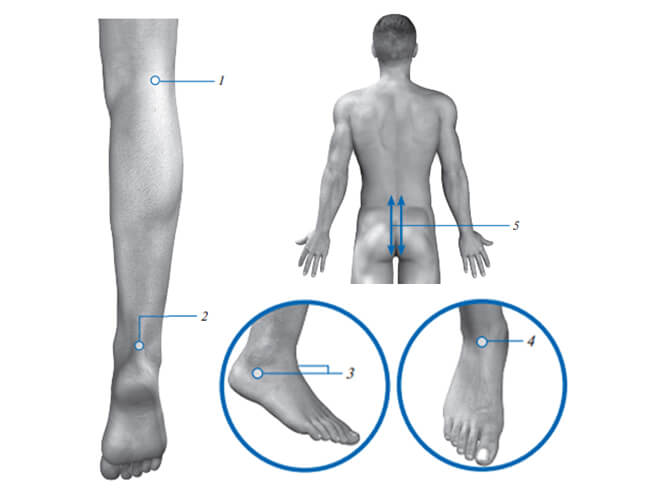

No.1

Exposure AreaPopliteal Pit

Areas around talocrural joint:

Frequency50Hz

Exposure Time5 min

No.2

Exposure Area– rear projection of the joint (Achilles' tendon)

FrequencyVariable mode 1000Hz to 2500Hz

Exposure Time2 min each per each zone

No.3

Exposure Area– side projections of the joint under the ankle on the right and on the left;

FrequencyVariable mode 1000Hz to 2500Hz

Exposure Time2 min each per each zone

No.4

Exposure Area– front projection of the joint;

FrequencyVariable mode 1000Hz to 2500Hz

Exposure Time2 min each per each zone

No.5

Exposure AreaAlong the lumbosacral spine (L4–Co), paravertebral, scanning

FrequencyVariable mode 1000Hz to 2500Hz

Exposure Time2 min per side